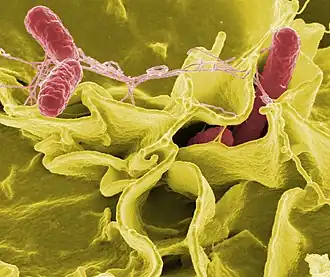

| Scanning electron micrograph of Escherichia coli rods | |||

Knowledge of bacteria

Although an estimated 43,000 species of bacteria have been named, most of them have never been studied.[15] In fact, just 10 bacterial species account for half of all publications, whereas nearly 75% of all named bacteria don’t have a single paper devoted to them.[15] The best-studied species, Escherichia coli, has more than 300,000 studies published on it,[15] but many of these papers likely use it only as a cloning vehicle to study other species, without providing any insight into its own biology. 90% of scientific studies on bacteria focus on less than 1% of species, mostly pathogenic bacteria relevant to human health.[15][16]

While E. coli is probably the best-studied bacterium, a quarter of its 4000 genes are poorly studied or remain uncharacterized. Some bacteria with minimal genomes (< 600 genes, e.g. Mycoplasma) usually have a large fraction of their genes functionally characterized, given that most of them are essential and conserved in many other species.[17]